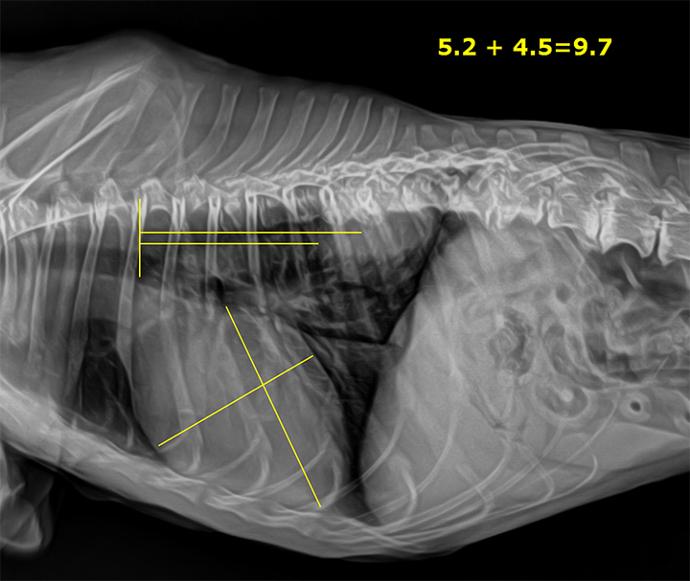

Système radiographique vétérinaire VETSMART DR